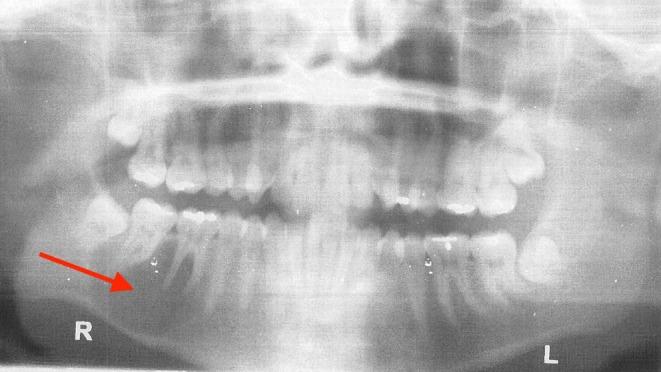

下颌骨特发性骨腔的诊断与治疗:一例报告

Idiopathic bone cavity of the mandible can often be identified in a radiographic exam. If detected, physicians should conduct follow-up every 3-6 months, with surgical intervention considered only if the lesion becomes large or symptomatic.

下颌骨特发性骨腔常在影像学检查中被发现。若检测到,医生应每3 - 6个月进行随访,仅当病变变大或出现症状时才考虑手术干预。